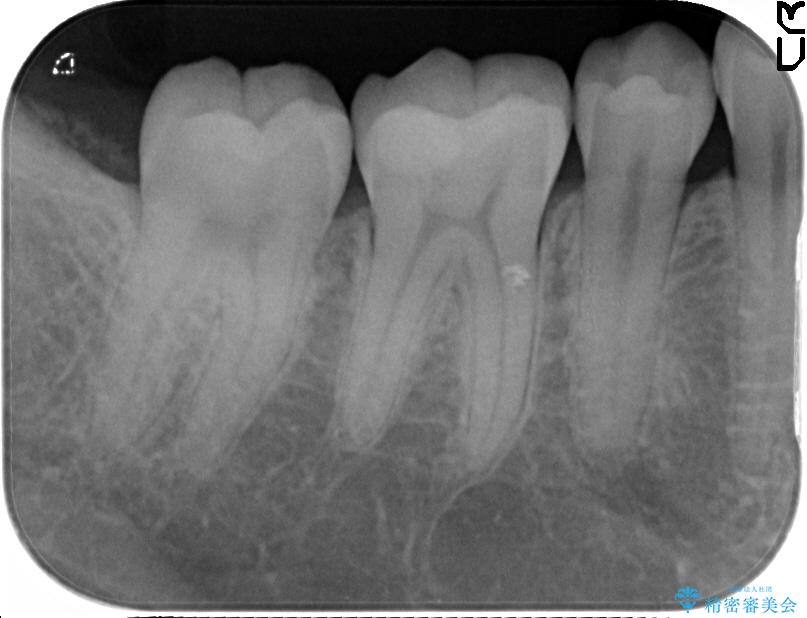

診査をした結果、顎左右の前から6番目の歯に深い虫歯があったため、詰め物(インレー)タイプで修復していく(e-max プレスインレー)での治療を行いました。

今回は歯の黒ずみを気にしてご来院されましたが、診査をしますと神経の治療が必要になる一歩手前の状態である神経の近くまで虫歯が広がっていました。

無症状でも歯の奥深くまで進行していることが多くあり、できるだけ早めの治療をおすすめいたします。